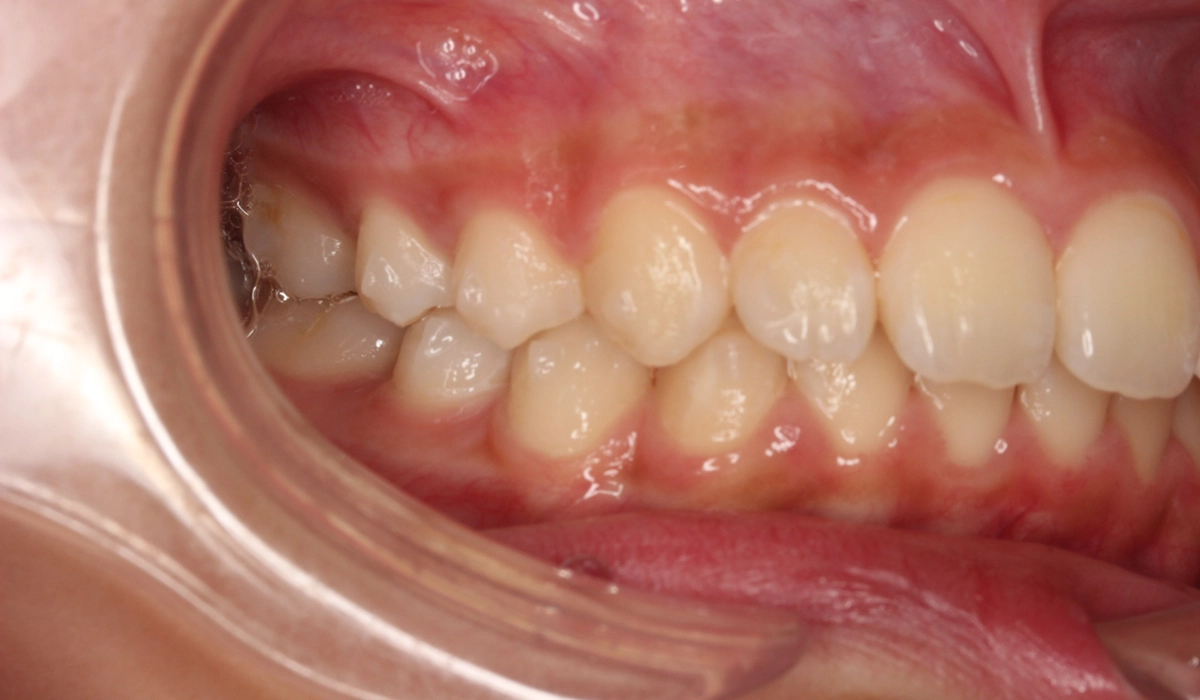

術前:右側

術後:右側